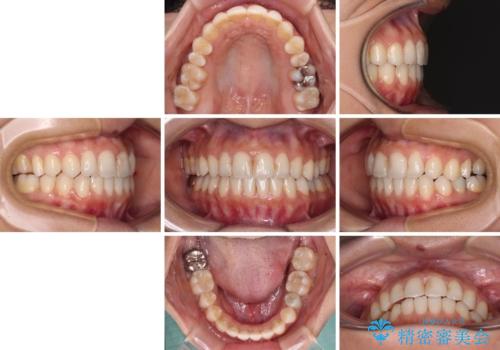

- オープンバイトのため、話しているときの見た目が気になるとのことで来院された患者様です。

下顎骨は左側にシフトしており、咬み合ったときには奥歯と前歯の一部しか接触していない状態でした。

骨格的な左右差は歯列矯正は改善できないため、上下歯列が全体的に接触することをゴールとしてインビザラインにて矯正治療を行うこととしました。

前歯のデコボコの解消と並行して上下の奥歯を圧下させるようにすることで、前歯を接触させるように計画しました。

上下の隙間に舌が入り込むことがオープンバイトの原因であったため、舌の筋肉のトレーニングも並行して行い、後戻りの抑制を図りました。